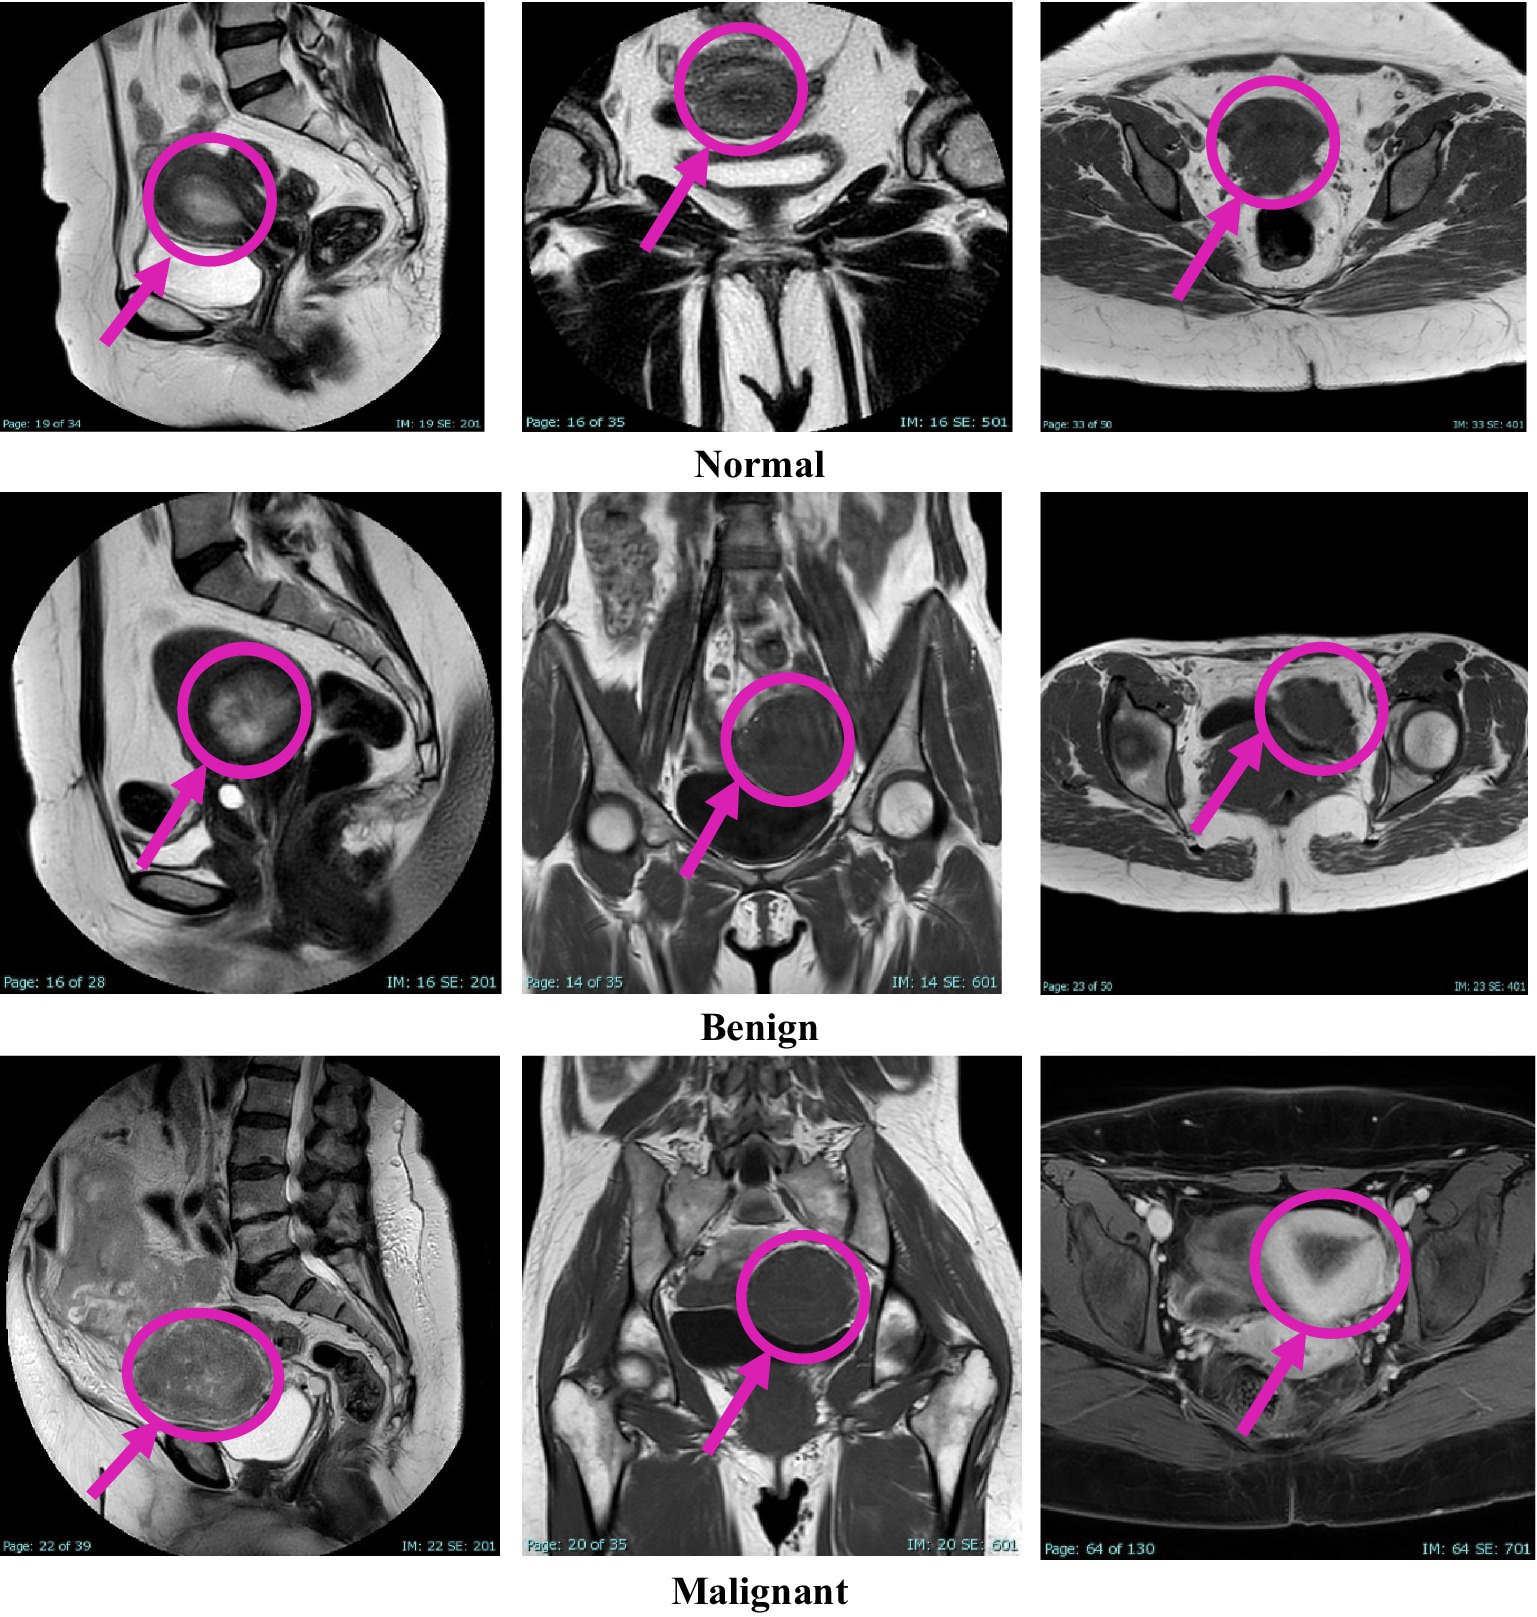

This study was approved by the Institutional Review Board (IRB) at King Abdullah University Hospital, Jordan University of Science and Technology (JUST). Radiologists retrospectively diagnosed patients using MRI data collected over 4 years, from early 2020 to early November 2024. Image extraction and dataset assembly were finalized during the data collection window between December 2024 and March 2025, during which anonymized and pre-evaluated images were organized into a structured dataset. The dataset comprises 1,814 MRI images collected from 450 female patients, aged between 18 and 85 years. The cases were classified into three diagnostic categories: normal, benign, and malignant, with each case represented by three imaging planes—sagittal, coronal, and axial. All images were acquired using the Ingenia Ambition 1.5 T Sand MRI scanner and exported in JPG format at a standard resolution of 720 × 720 pixels. To ensure the accuracy of the classification, KAUH obstetrics and gynecology physicians independently reviewed the imaging data. Table 1 shows the distribution of the KAUH-UCM dataset, with a representative sample from each group shown in Figure 2.

Figure 2

Figure 2. An example from the KAUH-UCM image dataset.